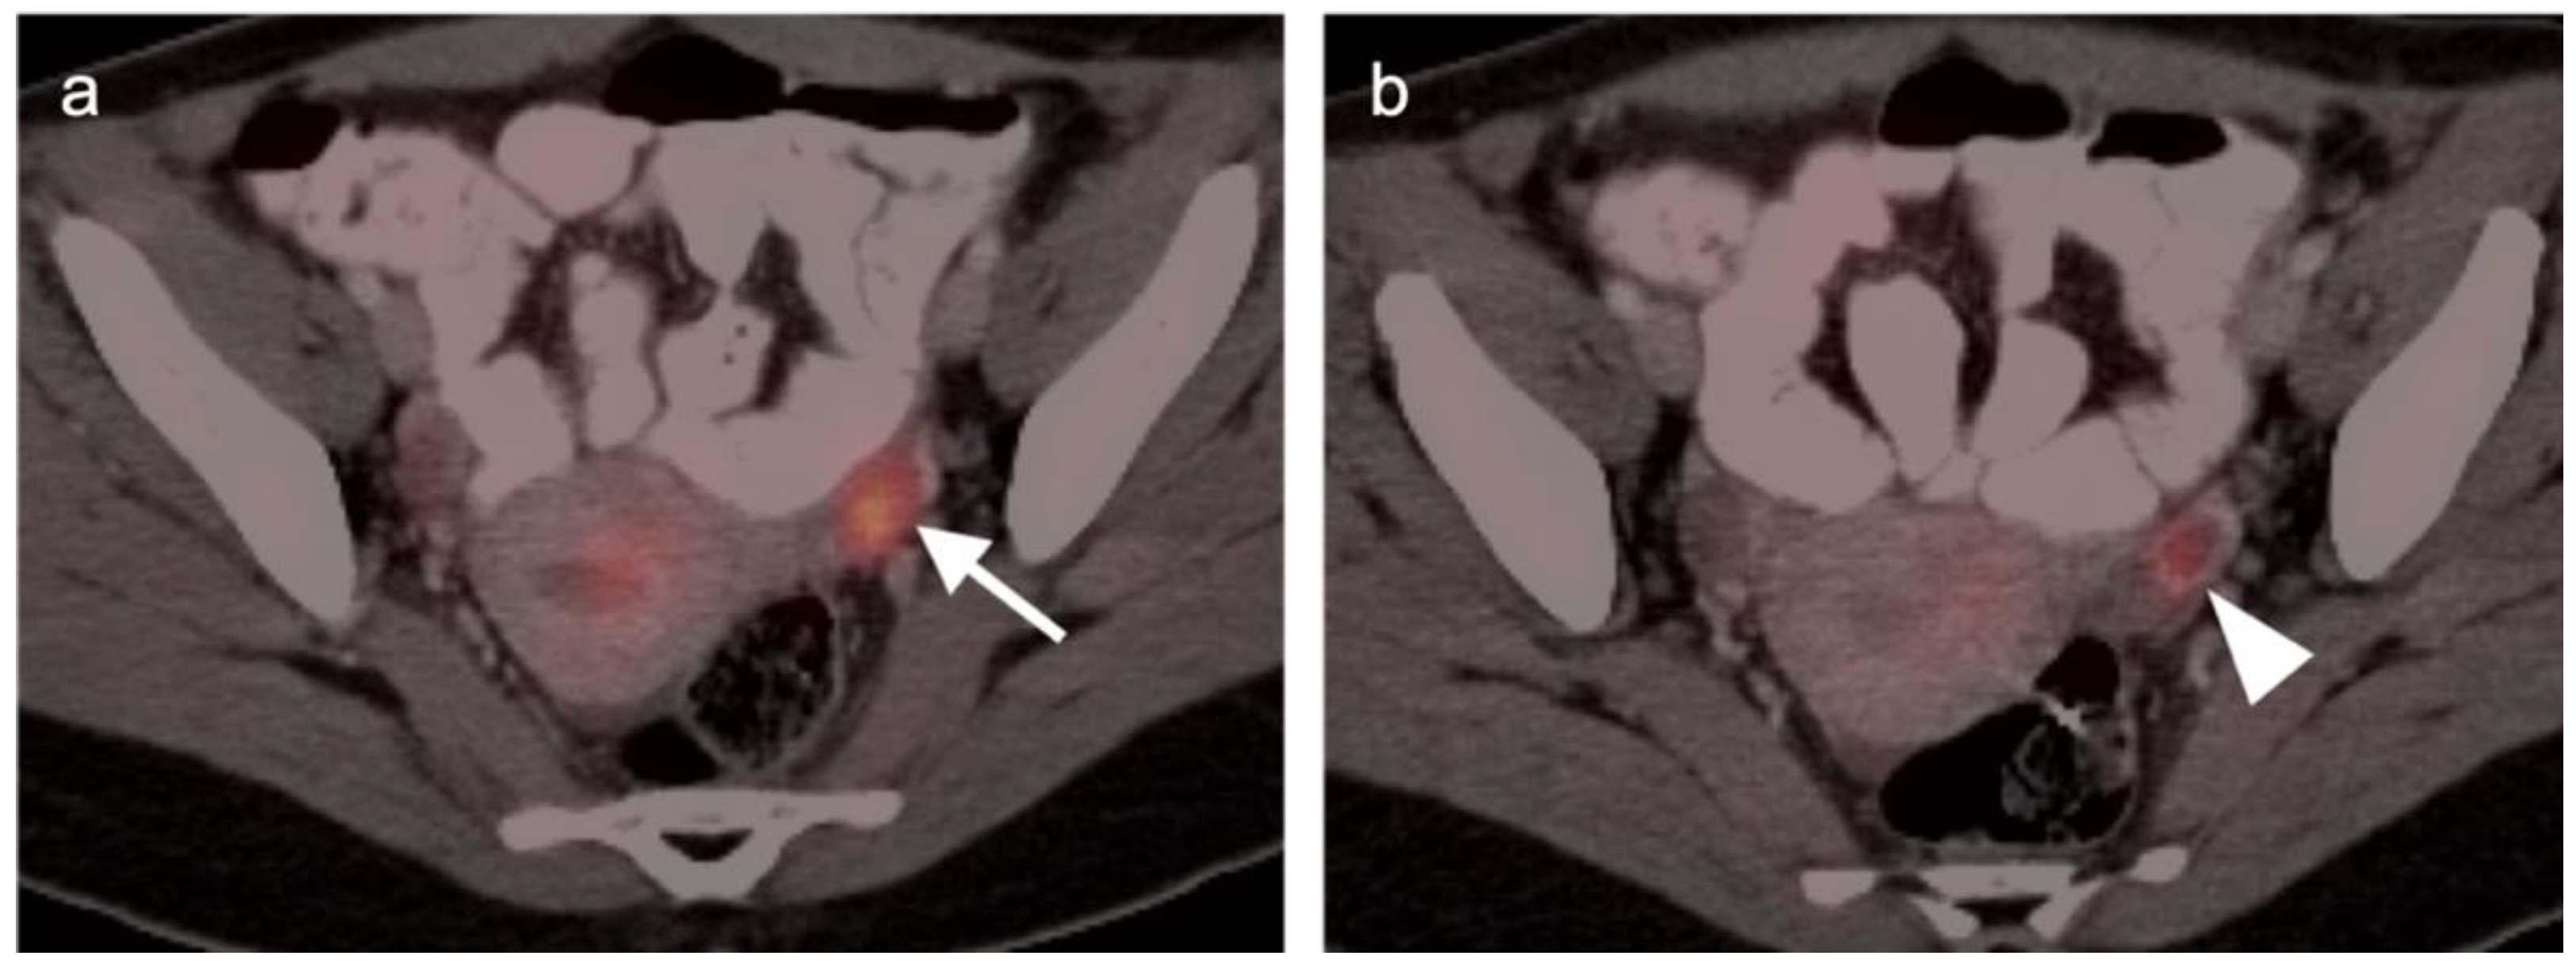

2.4. Cervical Cancer